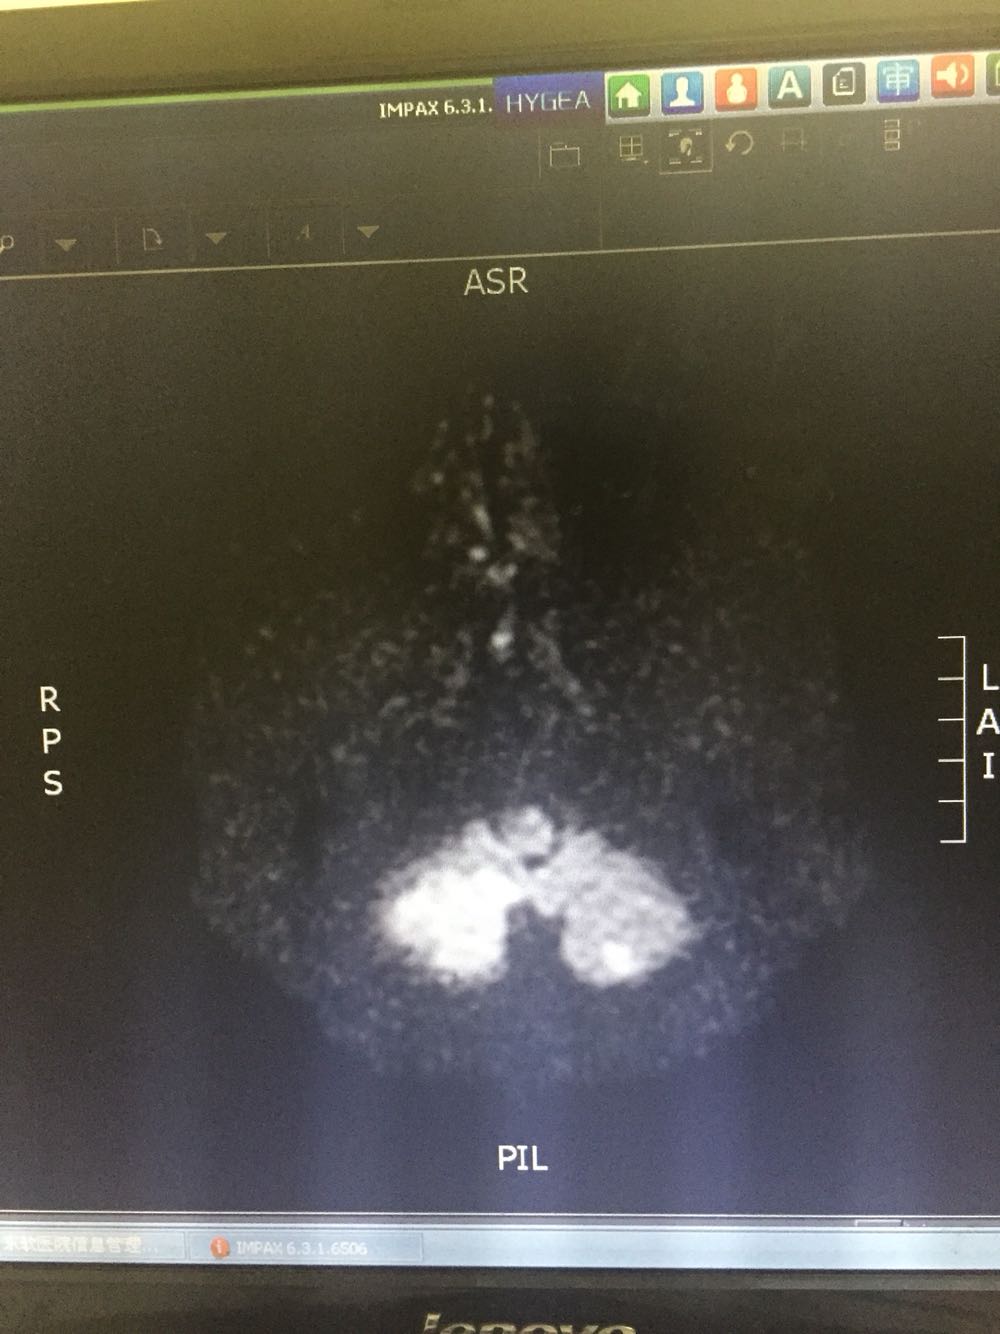

76岁女患,因眩晕三小时入院 既往高血压3年,冠心病史 该患者于入院前三小时无明显诱因出现眩晕,伴有恶心、头痛,无呕吐,病程中无肢体活动障碍,无言语不清,无意识障碍及尿便失禁,不伴有耳鸣及听力减退,为求进一步诊治而来我院。 血、尿化验未见明显异常

诊断:脑梗死、高血压 治疗:改善循环、抗血小板聚集、营养神经、调控血压对症治疗

主要注意与基地动脉尖综合症相鉴别。该患者右侧P2及左侧P3段局限性狭窄